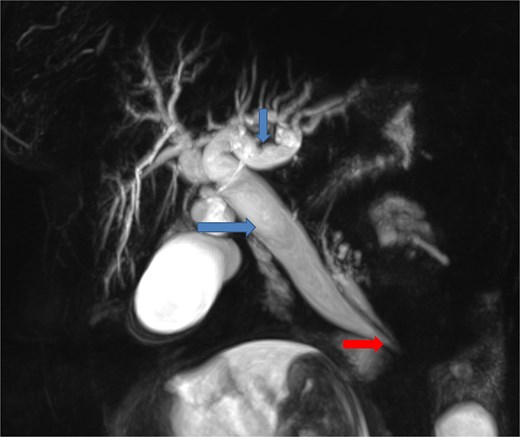

Due to the acute presentation and unavailability of emergency magnetic resonance imaging (MRI), a contrast-enhanced computed tomography (CT) scan of the abdomen was performed with strict fetal protection measures (lead apron, low-dose protocol). The pancreas appeared normal with no signs of inflammation, necrosis, or peripancreatic fluid. Unexpectedly, the scan revealed a duodenojejunal intussusception, likely originating from the fourth portion of the duodenum (D4), involving invagination of a proximal jejunal loop (Fig. 1). A typical pseudokidney sign was observed on sagittal reconstructions (Fig. 2). There was no identifiable lead point such as a mass or polyp. The intussusception was seen tractioning the distal common bile duct, leading to marked extra- and intrahepatic bile duct dilatation (Fig. 3).

Coronal contrast-enhanced CT image showing the intussusception causing traction on the distal common bile duct (arrow at the bottom), resulting in significant upstream dilatation of the extrahepatic and intrahepatic bile ducts (two arrows at the top).